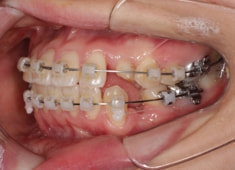

治療中